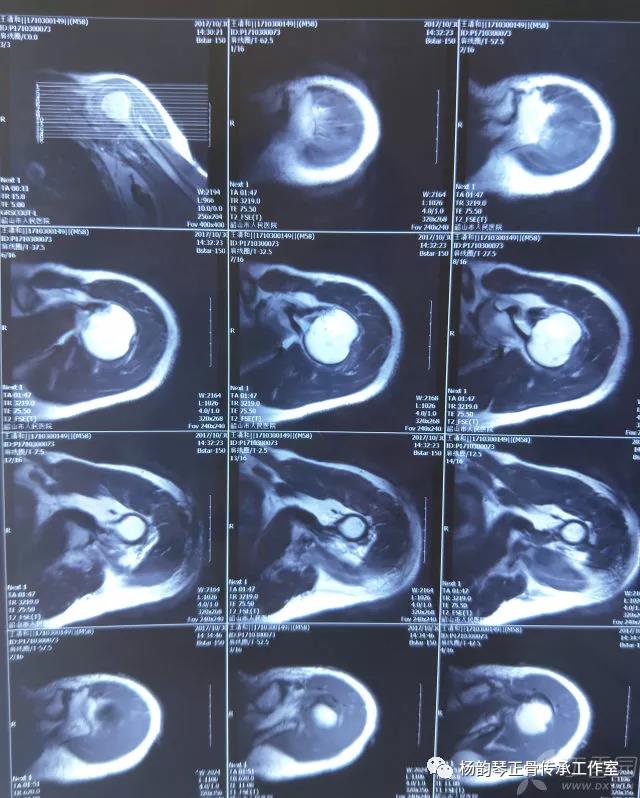

就诊我院后完善CT,诊断明确——左肩关节后脱位:

予以手法复位后拍片复查显示“灯泡征”消失,复位成功。讨论:肩关节后脱位在临床较为少见,特别是影像科经验不足很容易漏报,所以我们临床医生一定要自己仔细阅片,同时要结合体查来进行诊断,防止漏诊。肩关节后脱位时体查也有明显特征:肩关节前方明显变平,喙突较平时明显凸起容易触及,而肩关节后方明显丰满,上臂一般处于内旋内收位,无法主动外旋外展。肩关节后脱位的手法复位相对于前脱位的复位来说也比较容易。患者一般可以取坐位,助手自患侧腋下环抱患者稳定患者躯体,术者一手拉患肢上臂稍牵引内旋,一手自后方推顶肱骨头一般可以复位,如果单纯推顶无法复位也可以术者两手握住伤肢缓慢外展并沿肱骨纵轴牵引,然后逐渐外旋上臂即可复位。整复完成后可以把持患肢作肩关节各个方向的小幅度被动活动,防止肩关节粘连,肩关节后脱位的固定方法与肩关节前脱位的固定方法不同,应将患肢置于上臂外展、后伸、外旋位固定,即外展30度、后伸30度和轻度外旋位,用外展支架固定3周后,循序渐进开始肩关节功能康复。